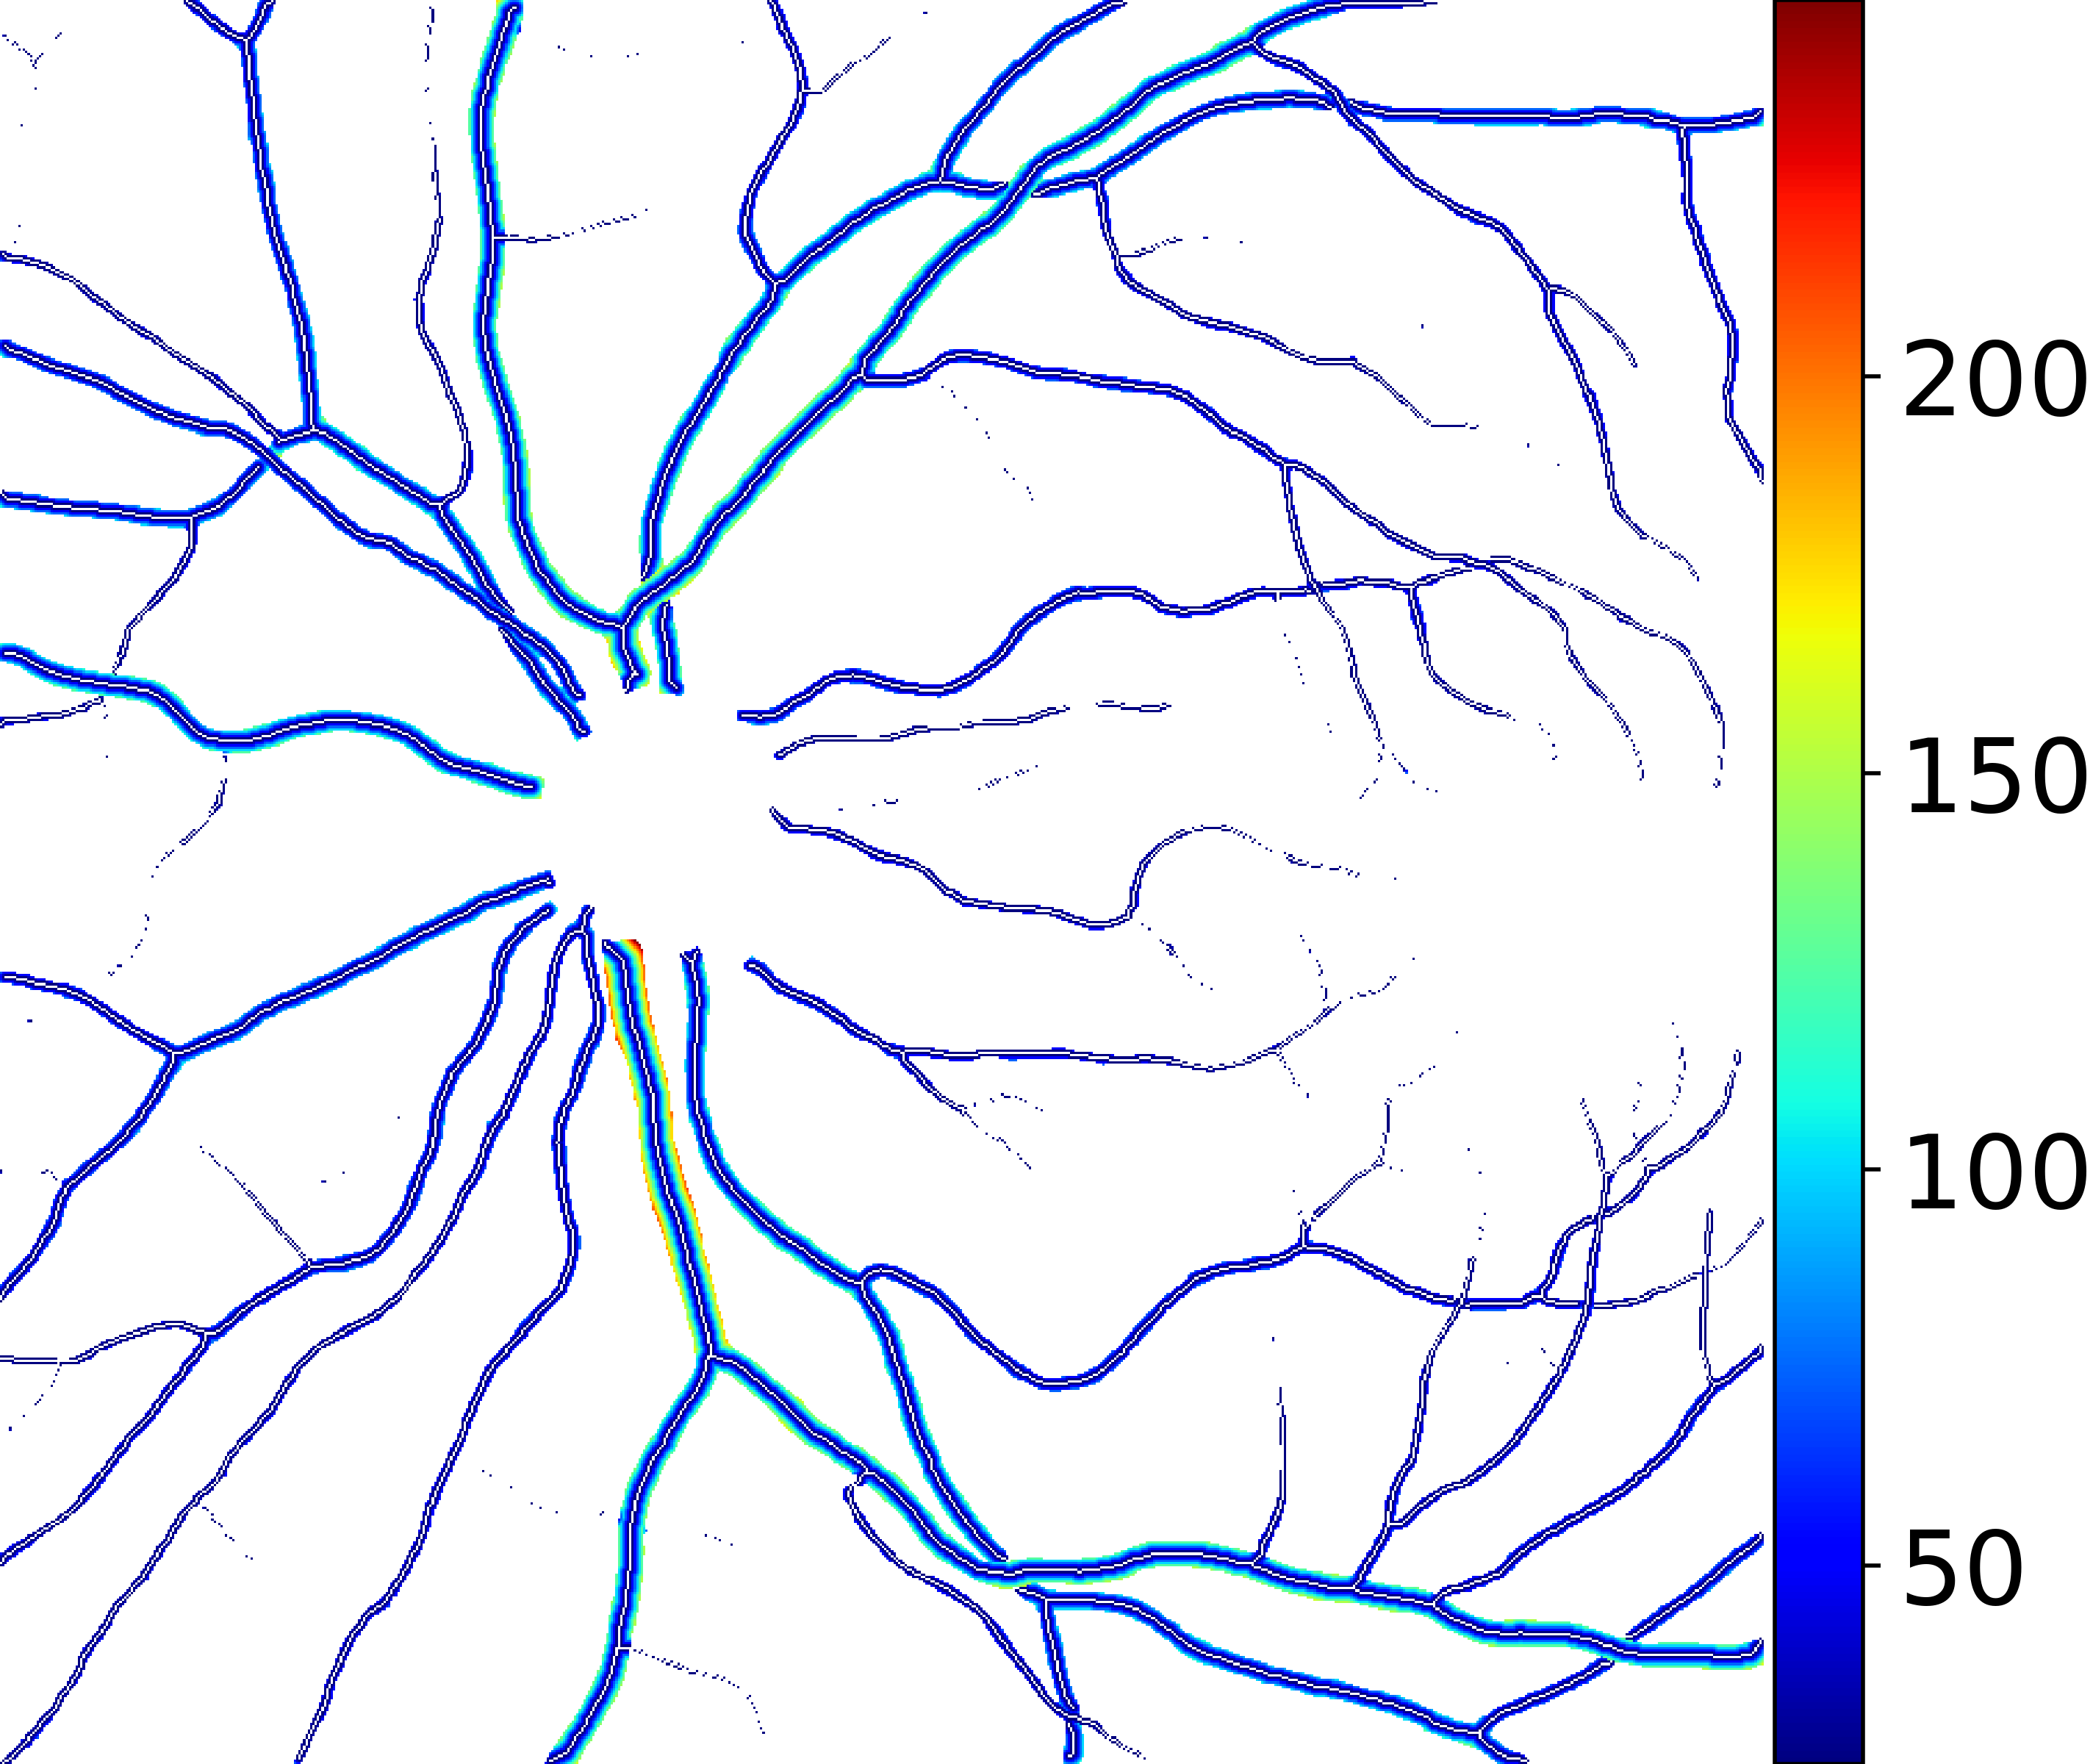

IV-C Vessel Width Estimation

From the segmentation predicted by the SegRAVIR network, our model measures the diameter of the arteries and veins. To this end, the segmentation probability map is first thresholded, using a constant value of 0.5, to obtain the medial curves of the vessels by iteratively identifying and removing border pixels while maintaining vessel connectivity, in an approach similar to the thinning algorithm presented by Zhang et al. [49]. Then, the distance transform of the medial curve mask is multiplied with the segmentation mask in a pixel-wise manner. The result is the diameter distance map with respect to the medial curves of the segmented vessels.

VI-B Vessel Width Estimation

Table VI presents a quantitative comparison of the measured diameters using the segmentation outputs of SegRAVIR and competing approaches. Using the pixel-wise annotated masks, the reference average diameter of the arteries and veins in the test set of the RAVIR dataset were measured as and , respectively. According to our analysis, SegRAVIR can accurately measure the diameter of the vessels and it achieves the smallest MAPE among the competing approaches. Specifically, in comparison to CE-Net, Iter-Net, and DU-Net, respectively, SegRAVIR is on average , and more accurate in terms of MAPE for the measured diameter of arteries and , and in terms of MAPE for the measured diameter of veins. Fig. 6 presents qualitative comparisons of reference and SegRAVIR estimated diameter maps.

(a) (b) (c)